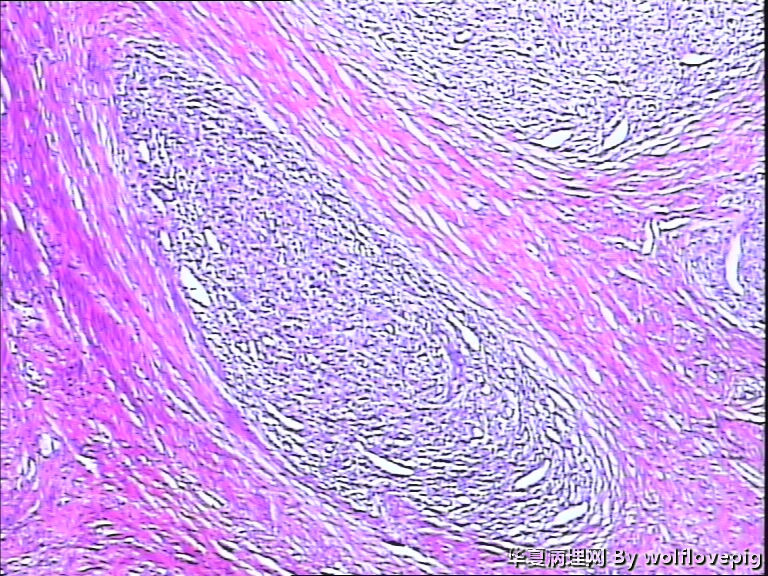

37y,肌壁间可见多个小结节0.2~0.8cm。

图3